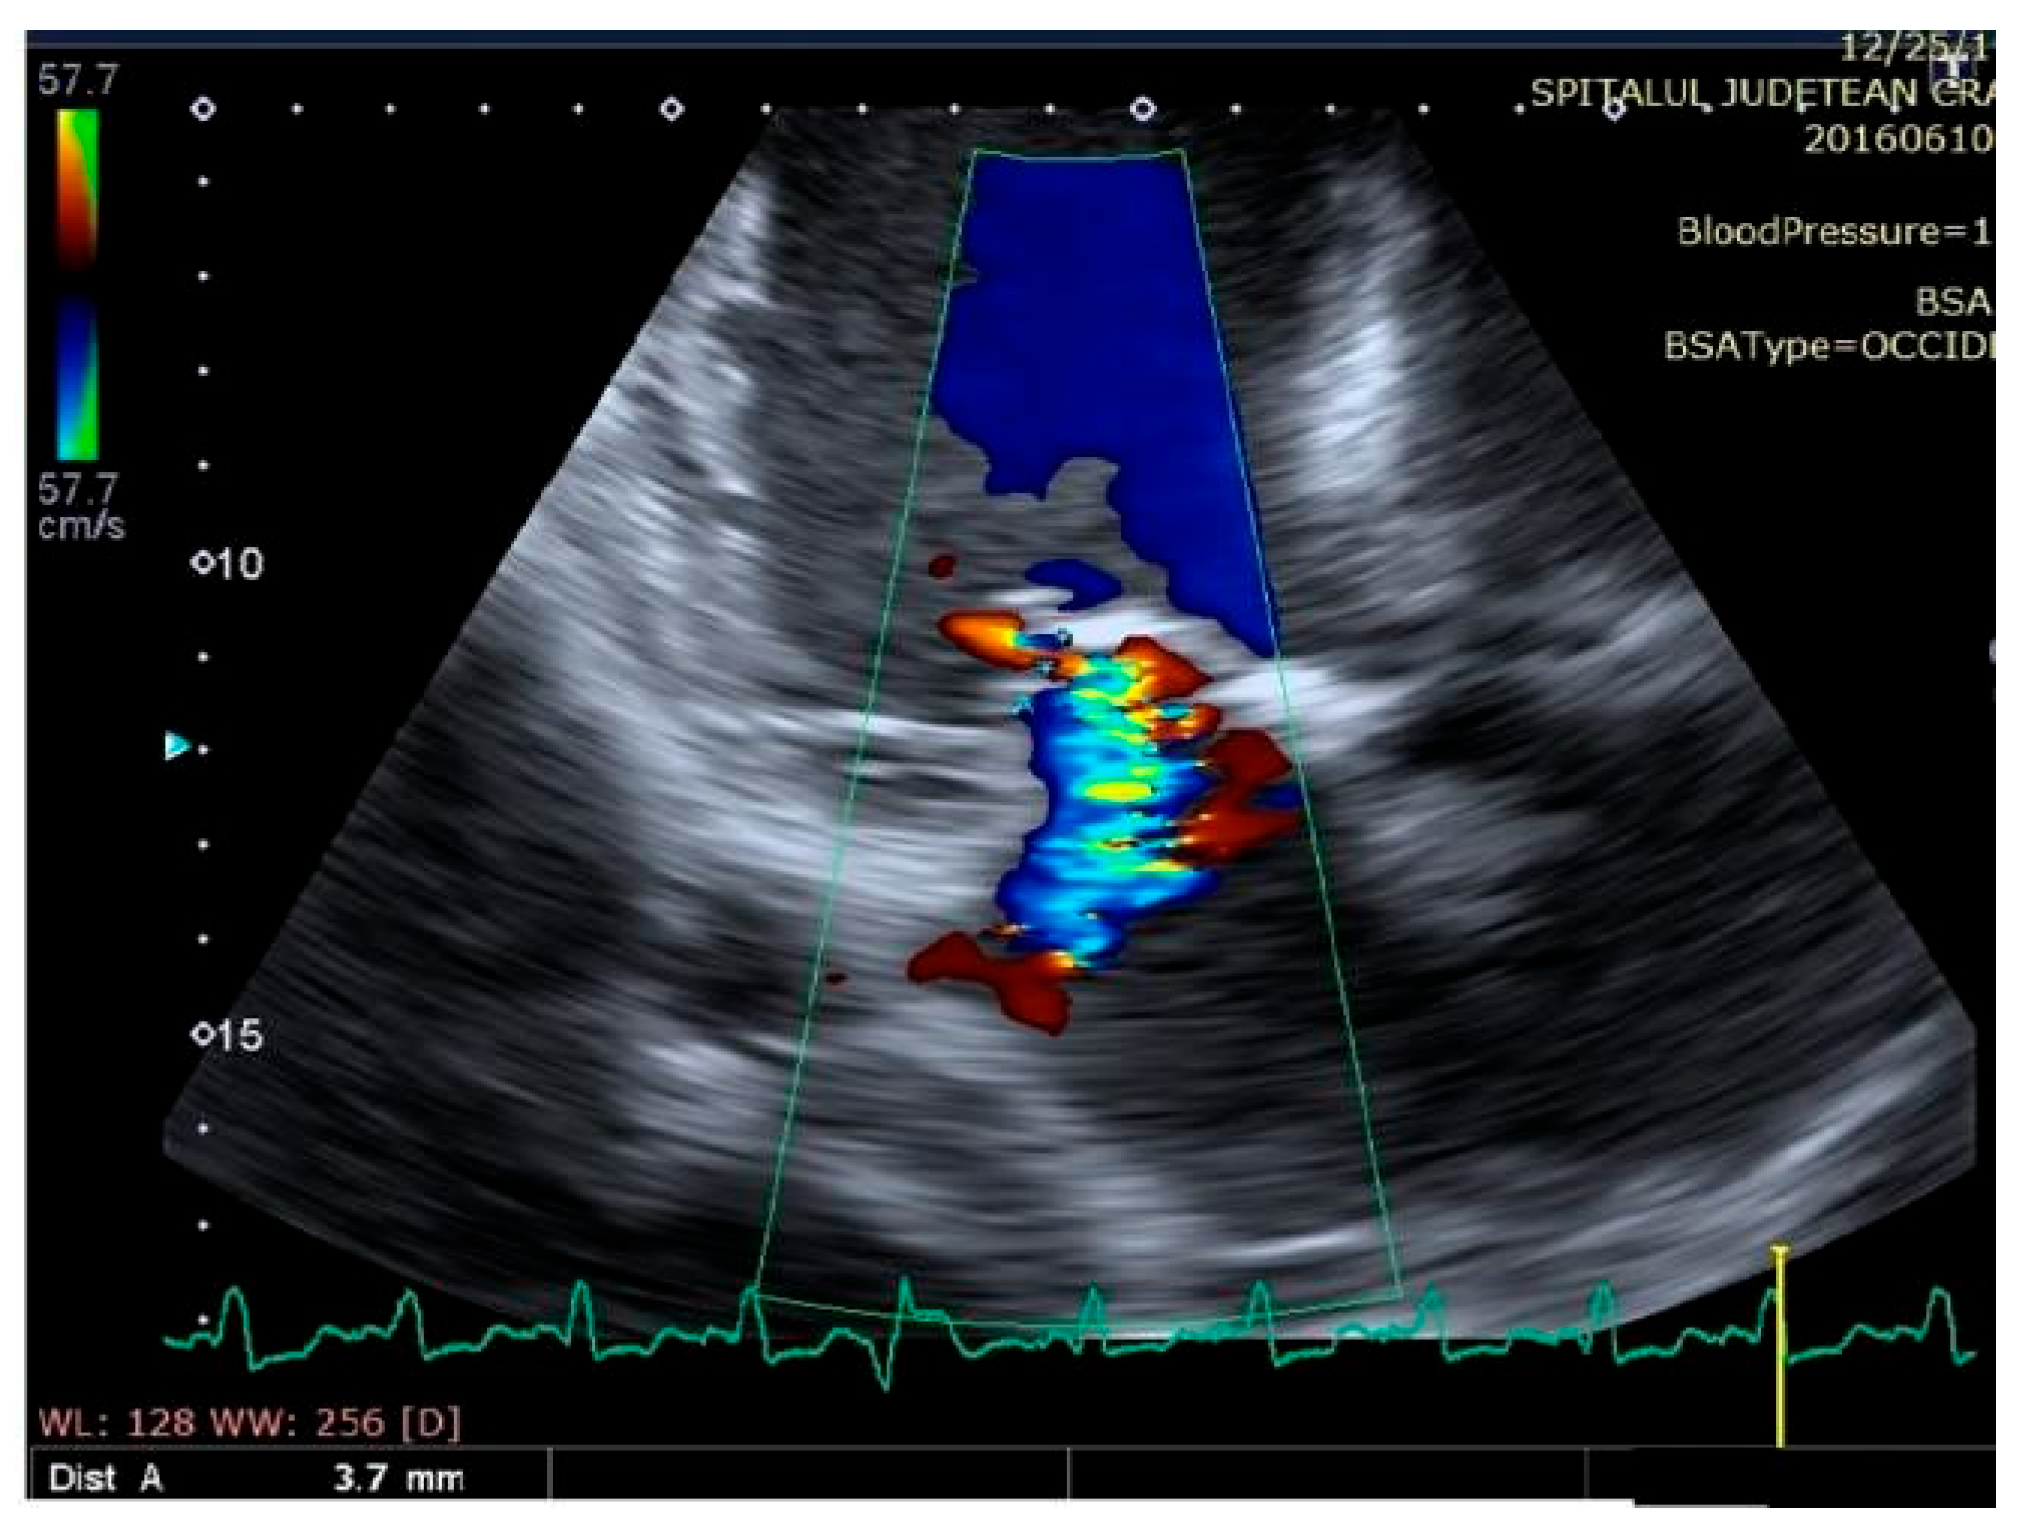

Mitral regurgitation (highlighted as multicolored mosaic pattern, green and yellow), before therapy with a cardiac resynchronization device.

Figure 7.